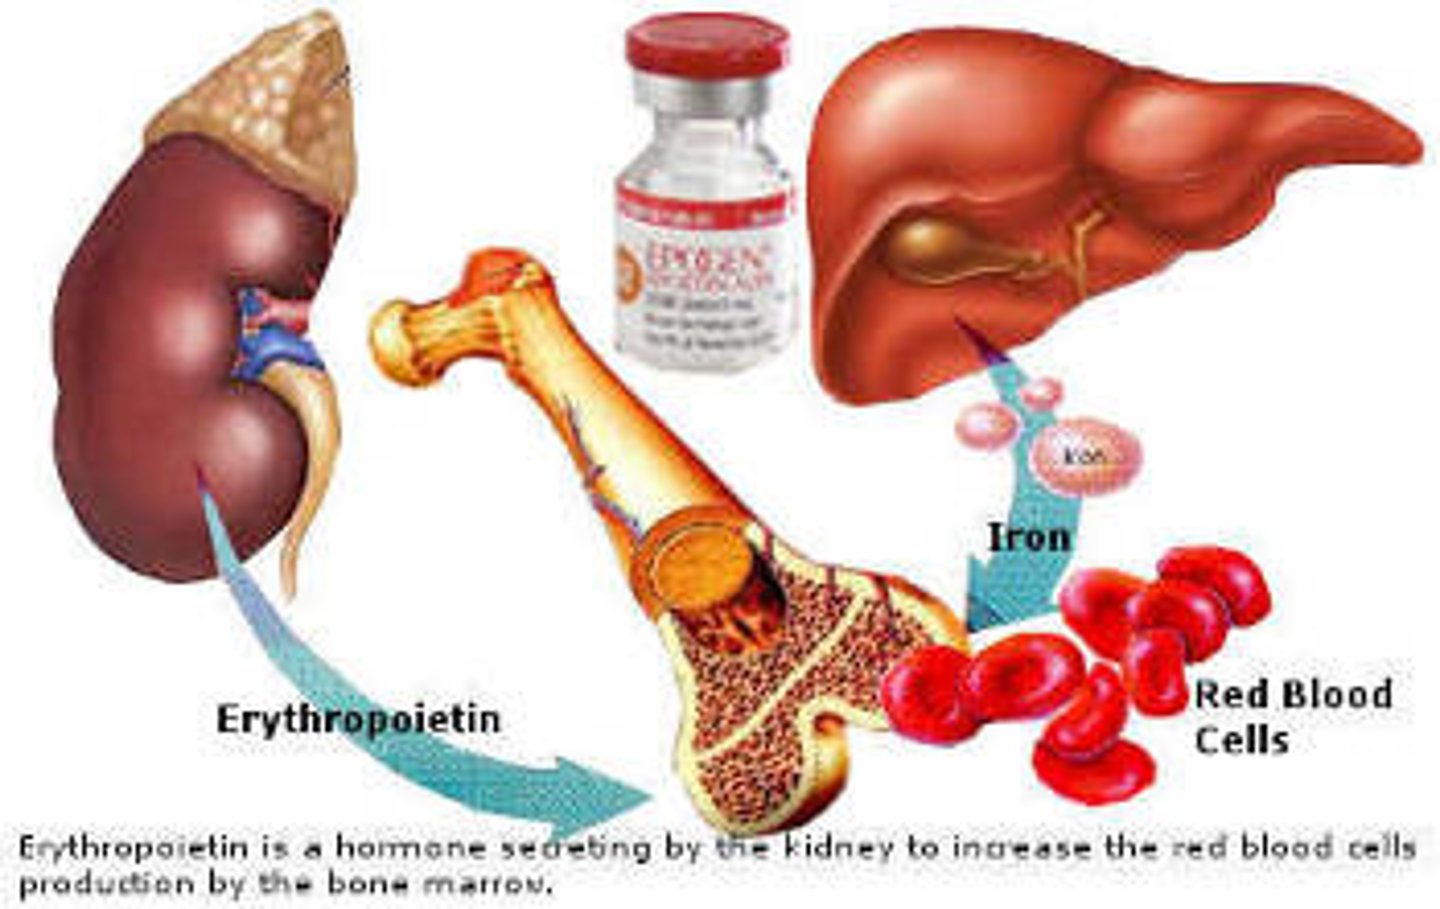

EPO

Erythropoietin; promotes growth of red blood cells